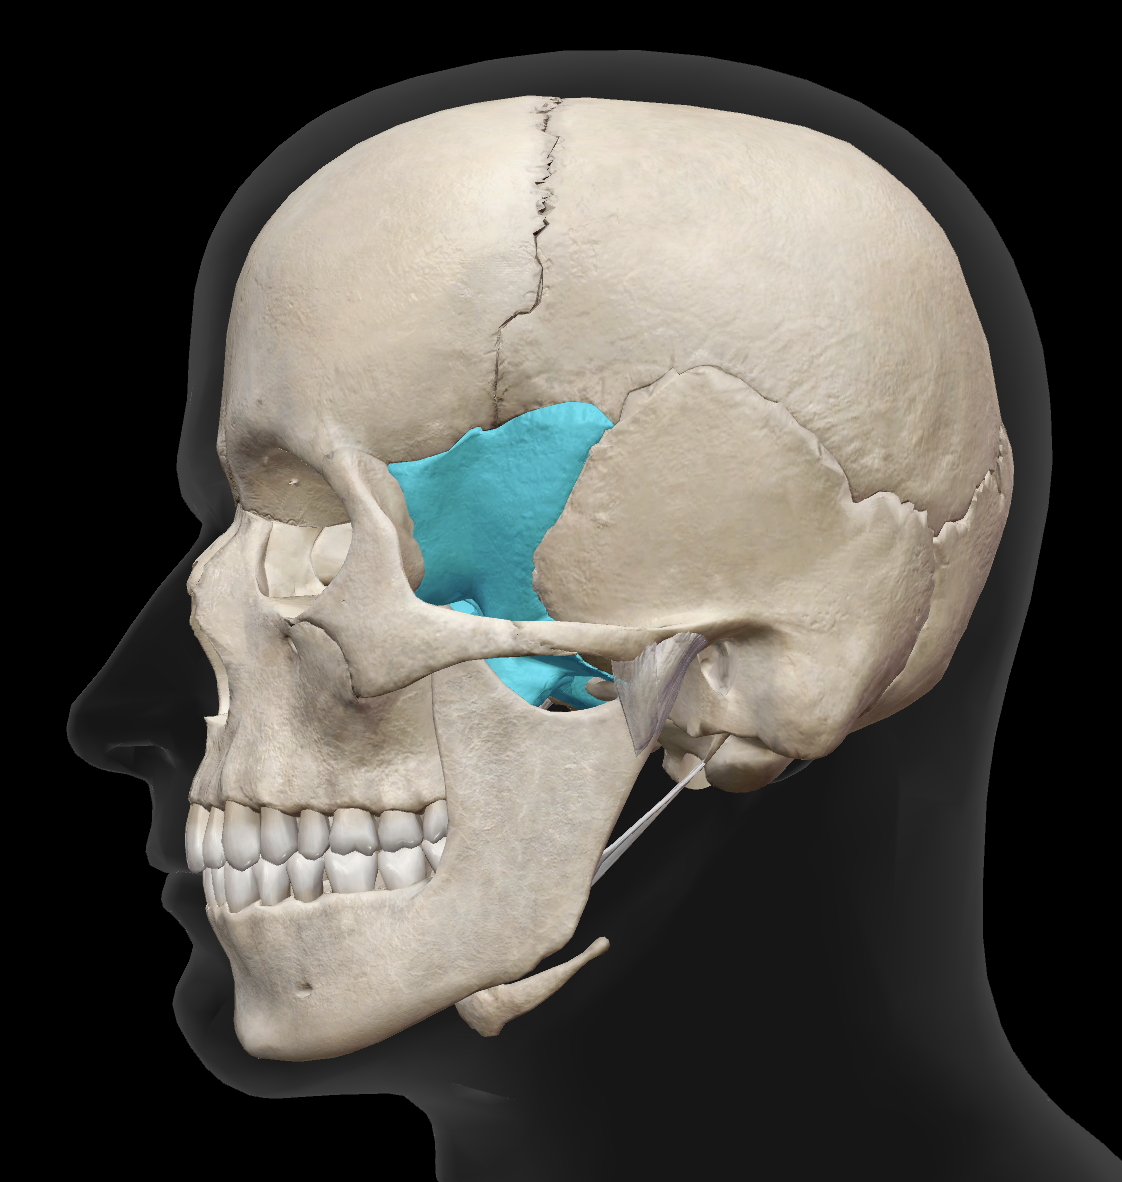

What bone is highlighted?

zygomatic bone

What is bone 5?

sphenoid bone